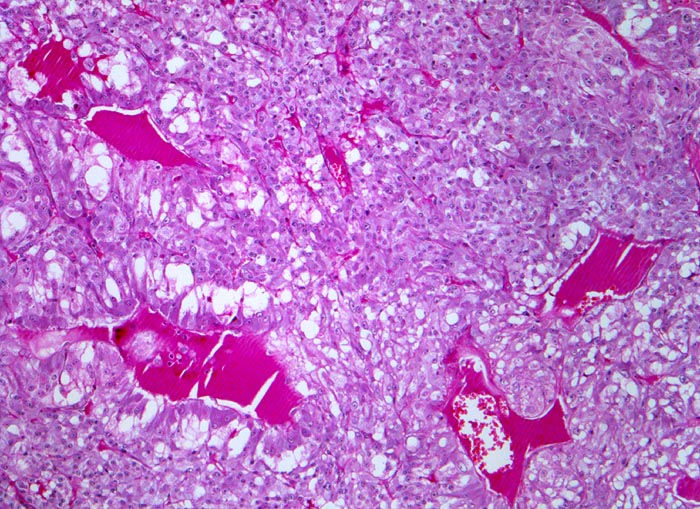

• Unscharf begrenzter, gefässreicher Tumor ausgehend vom Nebennierenmark.

• Zungenförmige Infiltration der angrenzenden Nebennierenrinde. Die Zellen der Nebennierenrinde haben reichlich eosinophiles Zytoplasma und kleinere Kerne als die Tumorzellen.

• „Zellballen“ umgeben von schmalen Bindegewebssepten mit kapillären Gefässen.

• Polygonale Tumorzellen mit reichlich granuliertem basophilem Zytoplasma und rundovalen Kernen mit uniform feinkörnigem Pfeffer und Salz Chromatin sowie prominentem Nukleolus.

• Herdförmig Tumorzellen mit sehr grossen polymorphen Zellkernen (links oben).